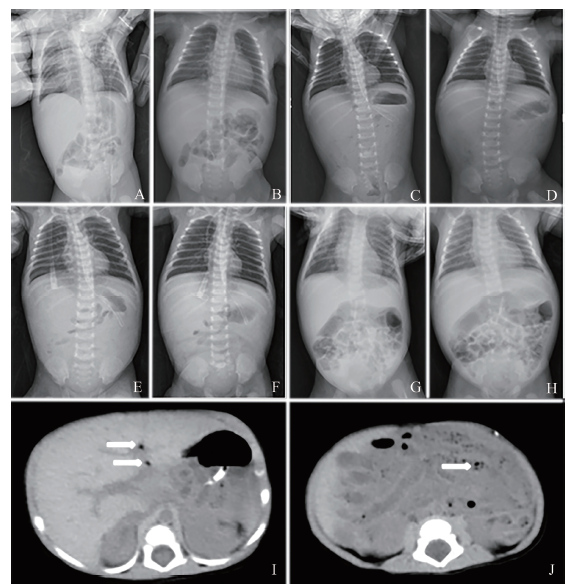

图1 一例CV A6感染致NEC的新生儿影像学检查图

A、B:入院时急查腹部立位及卧位片,双膈下未见明显游离气体,腹部肠管见少许积气,肠管未见明显扩张及气液平,肠壁未见明显积气影,门静脉区未见明显积气;C、D住院第4日腹部立位及卧位片,腹部密实,大部分大小肠管未见明显充气,腹部见散在多发细线状、环状透亮影,肝门区周围亦似见线状透亮影(门静脉积气?),考虑新生儿NEC可能性大,立位左膈下内侧见可疑的少许透亮气体影,右膈下未见游离气体影;E、F:住院第5日腹部立位及卧位片,立位膈下未见明显游离气体影,门静脉积气及肠壁积气较前减少,小肠腔内积气较前增多;G、H:住院第26日腹部立位及卧位片,立位膈下未见明显游离气体影,门静脉及肠壁未见明显积气,小肠腔内积气较前增多;I、J:住院第5日腹部CT,肠管普遍性积液,肠壁稍厚,门静脉左支及其分支多发积气,拟NEC可能,I的箭头指示为门静脉积气,J的箭头指示为肠壁增厚

监测患儿生命体征并予止血、补液、光疗退黄等治疗,喂养不含乳糖奶,住院第3日黄疸消退,大便次数增多,排黄色黏液血便,体格检查示双下肢散在花斑纹,肢端稍凉,肠鸣音正常,粪便潜血(++++),降钙素原较前升高,不排除合并NEC、败血症的可能,予哌拉西林他唑巴坦75 mg/kg、每8 h 1次抗感染治疗。住院第4日患儿进食量减少,伴呕吐黄色胃内容物2次,精神反应差,反复排血丝便,体格检查示血压79/45 mm Hg,

神情疲倦,肤色较苍白,全身可见花斑纹,心率增快,呼吸不促,无发绀,腹软,肠鸣音存在,肢端凉,急查腹部立位及卧位片提示“NEC、肠穿孔?”,见图1C、D,考虑诊断为NEC、肠穿孔、感染性休克,予禁食、胃肠减压、生理盐水扩容、升级抗生素[美罗培南 20 mg/kg、每8 h 1次,青霉素30 U/(kg·d)],请小儿外科专家会诊,拟继续予保守治疗。加予补液、止血、输注血浆等处理后,患儿生命体征恢复稳定,精神反应好转,肤色转红润,全身花斑纹基本消退。住院第5日复查腹部立位及卧位片示立位膈下未见明显游离气体影,门脉积气及肠壁积气较前减少,小肠腔内积气较前增多,见图1E、F;腹部CT提示肠管普遍性积液,肠壁稍厚,门脉左支及其分支多发积气,拟NEC可能,见图1I、J。住院第6日患儿脑脊液检查未见异常,监测其生命体征平稳,精神反应好转,无发绀,腹软,肠鸣音正常,肢端暖和,胃肠引流出草绿色液体较前减少,临床症状逐渐好转。经禁食及抗生素治疗14 d后停用抗生素,重新开始喂养不含乳糖奶,患儿无腹胀、呕吐,住院第26日复查腹部立位及卧位片无异常,见图1G、H,住院第28日出院,按需喂养不含乳糖奶。出院诊断:NEC并肠穿孔、感染性休克;新生儿黄疸、新生儿贫血。患儿出院后我科收到粪便逆转录PCR(RT-PCR)结果:住院第2日、第23日粪便 CV A6阳性,补充诊断:新生儿CV感染。患儿出院后1个月、3个月、6个月及1年的门诊定期复诊结果均显示其体质量、身长达标,生长发育情况良好。